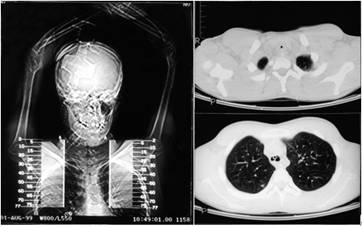

16岁男孩,疑“严重哮喘致呼吸困难”入ICU 7周前交通事故致头部外伤时在外院气管插管84h。入院后按照哮喘常规治疗,2天后因严重呼吸困难拟气管插管

声门暴露良好但7#气管导管刚通过声门2cm处遇到阻力,甚至无法通过bougie;将4.5#气管导管套在一根半硬导芯上,强行通过狭窄,然后送入气管导管,感觉明显阻力消失,通气良好,呼吸音正常

In summary,…Prolonged periods of tracheal intubation may lead to progressive tracheal stenosis presenting weeks or months later.

长时间气管插管可在数周或数月后发生进行性气管狭窄